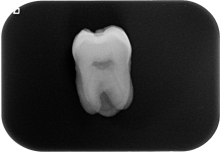

离体牙